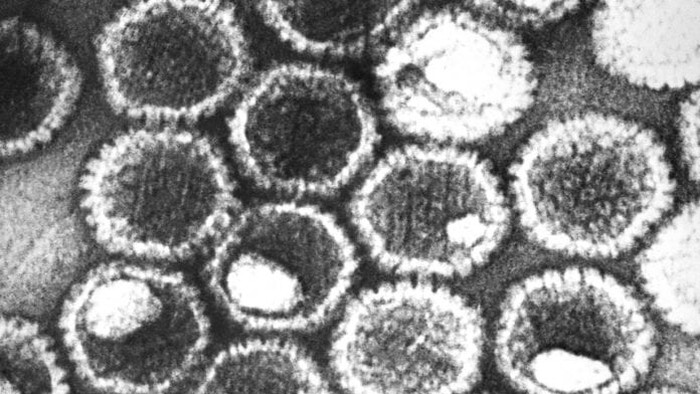

Jakarta - Tampilan cantik tapi menyeramkan di bawah mikroskop ini ternyata dari deretan mikroba! Seperti apa penampakannya?

Cantik Tapi Berbahaya, Potret Virus di Bawah Lensa Mikroskop